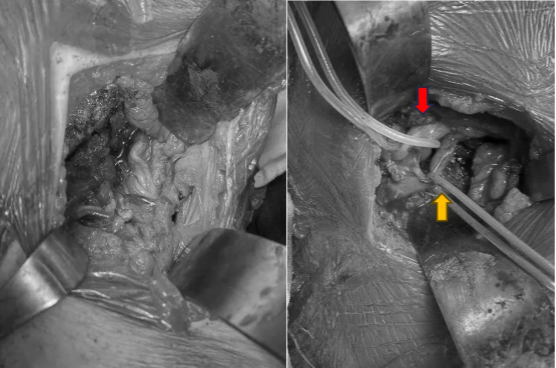

图示:手术采取前后联合入路

图示:左图前入路分离前方血管神经与肿瘤,右图示腋窝切口保护腋动脉(黄色箭头)及外侧索、后侧索神经(红色箭头)